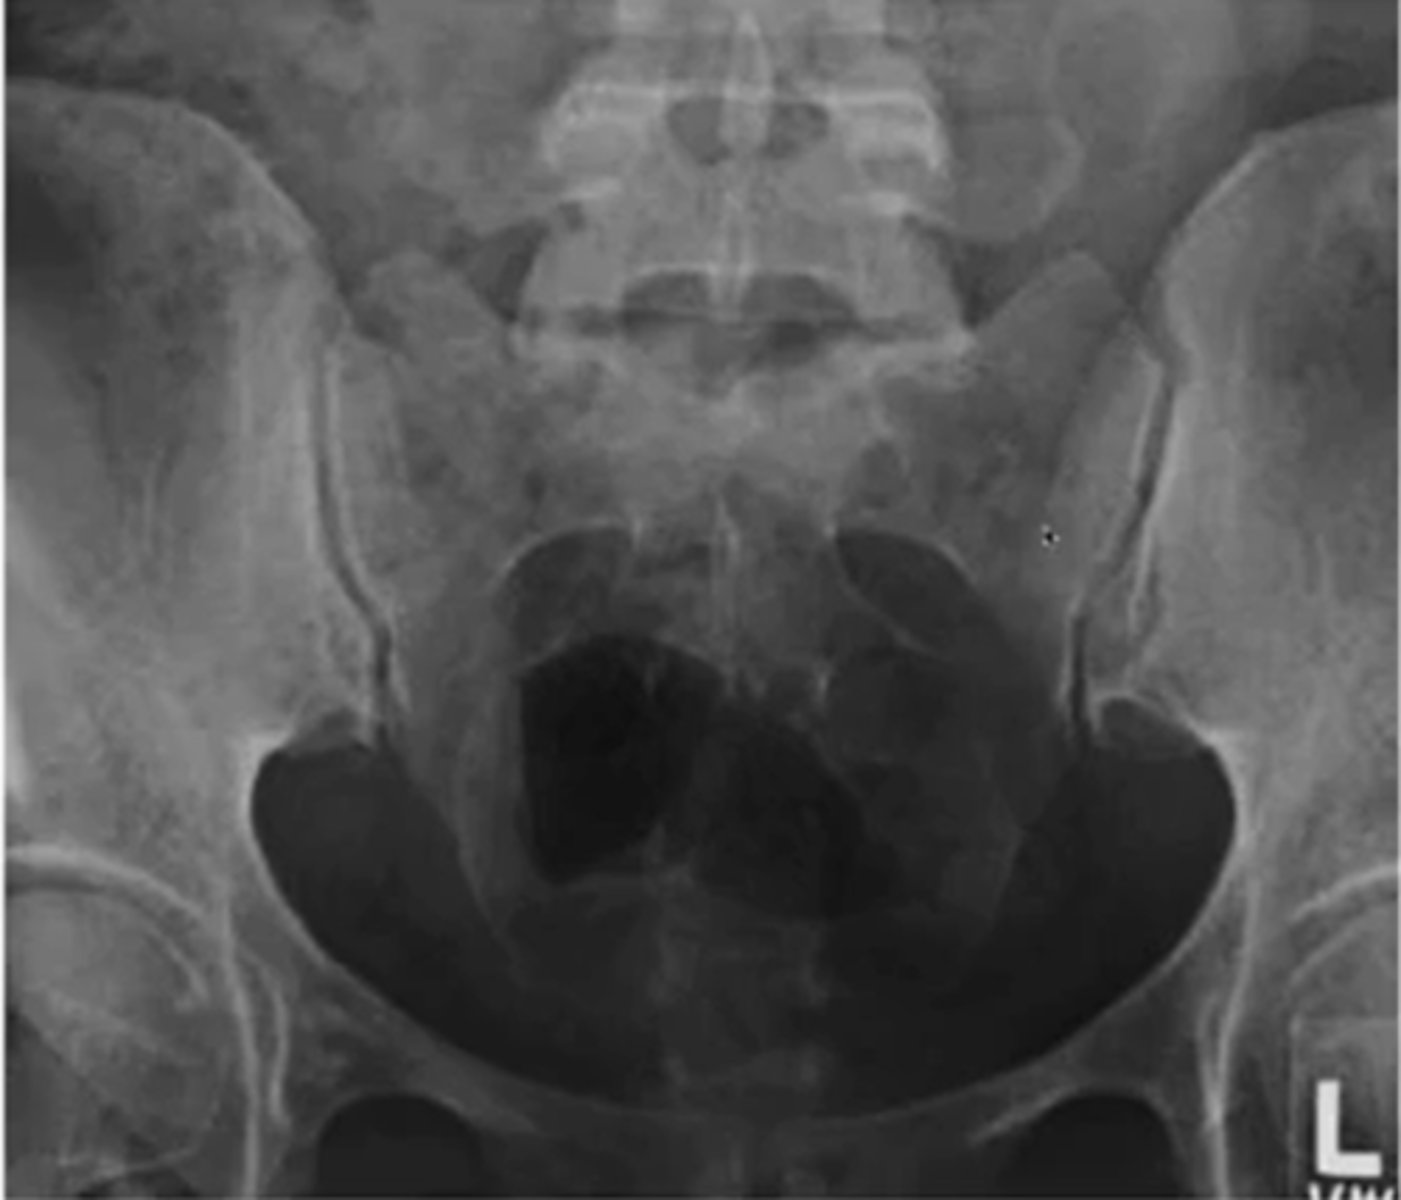

what are the three indications for hip radiograph

hip pain

avascular necrosis

stress fractures

for the pelvis what position is the hips for an AP view

IR 15-20 degrees

what are the three important portions of the acetabulum (ap view)

what position will the hip be if you want to see the medial portion of the femur (AP view)

frog leg